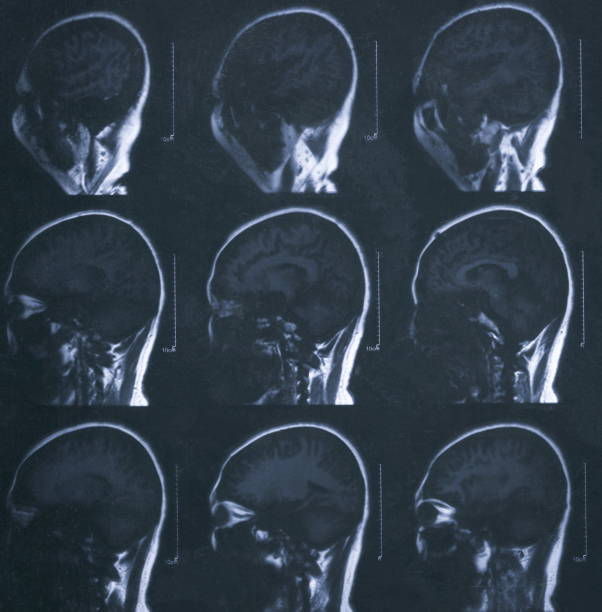

- Diagnostic Imaging: Conducting CT or MRI scans to map the brain's condition.